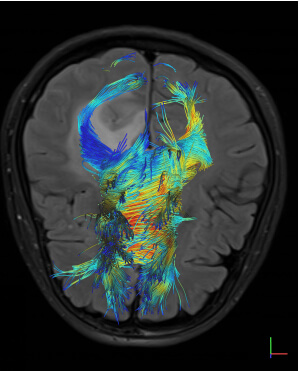

- Ειδικές τεχνικές state-of-the-art (Λειτουργική / Πολυπαραμετρική MRI, Φασματοσκοπία, Δεσμιδογραφία, Δυναμικές Αγγειογραφίες, Νευρογράφημα, Μελέτη Ροής ΕΝΥ)

- Δεσμιδογραφία (Τractography)